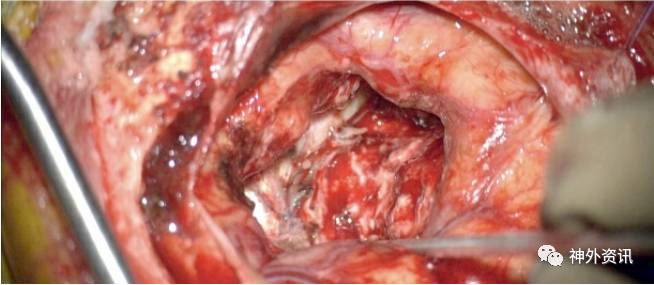

图6. 破裂的颞叶外侧面AVMs切除。注意粗大并动脉化的Labbe 静脉(第一行)。直切口开颅形成颞部骨瓣,经脑沟入路确认MCA远端粗大的供血血管(第二行)。这个MCA分支是从病灶边缘路过的血管,沿着它分出许多AVMs的供养血管。病灶恰位于此“过路动脉”的上方,当此动脉被轮廓化后,病灶也即切除 (最后一行)。可以看到切除完成后Labbe静脉颜色变深。保存此过路动脉对于避免远端缺血是很重要的。